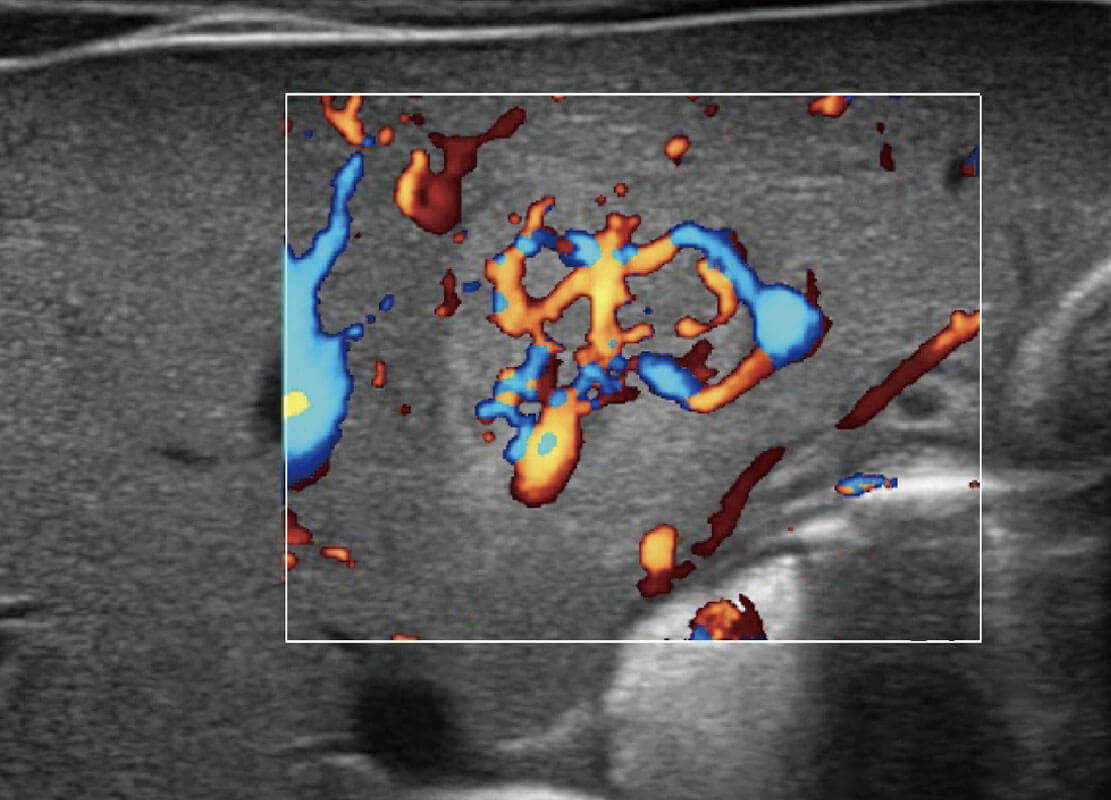

P60搭载一系列胎儿心脏成像技术,实现精细的胎儿心脏评估。

四腔心血流

P60搭载宽频带线阵探头、宽景成像、弹性成像技术,为您提供乳腺应用方案。P60支持高频相控阵探头、线阵探头、腹部高频探头、腹部微凸探头等,丰富的探头群搭载敏感的彩色血流成像,适用于新生儿多种脏器检测要求,满足新生儿筛查需求。

乳腺癌显微血流